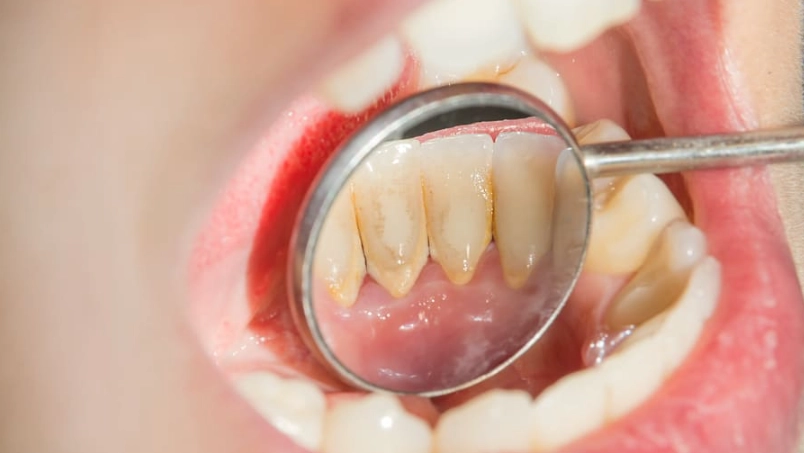

它剛形成時是軟的,可以用物理方式(刷牙)清除。但如果你沒清乾淨,大約24到72小時後,它就會開始礦化,吸收唾液中的鈣質,逐漸變硬成為「牙結石」。一旦變成牙結石,就像水泥糊在牆上,靠刷牙是絕對刷不掉的,必須由牙醫透過專業器械(如超音波洗牙機)才能清除。根據美國牙科協會的資料,牙菌斑是導致齲齒和牙周病的元兇。

關鍵點: 你對抗的是一個會「蓋房子」的細菌社群。清潔的黃金時間是在它軟軟的時候,一旦它「地基」穩固了,你就得找專業人士幫忙了。